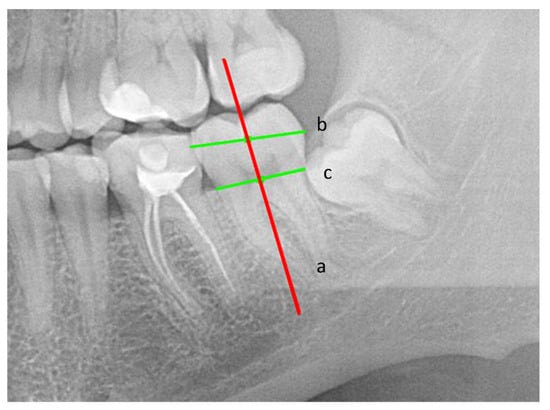

2.1.1. Plotting the Lines Necessary to Evaluate the Impaction of an Impacted Mandibular Third Molar

- Long axis of the tooth (a);

- Occlusal plane (A);

- Tangent to the anterior margin of the mandibular ramus (B).